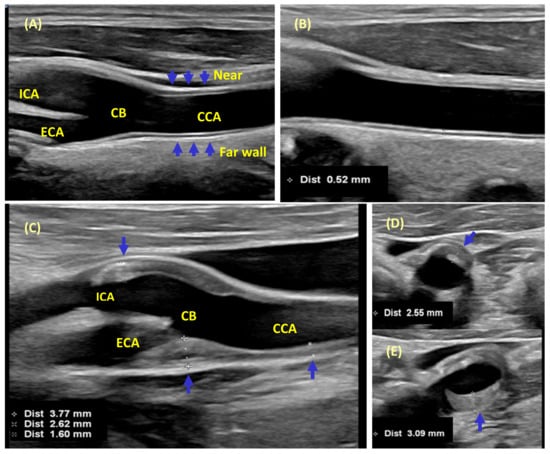

| Mannheim IMT Consensus, 2012 [59] | Definition: CIMT is a double-line pattern visualized by ultrasound on both walls of the CCA in a longitudinal image, which consist of the leading edges of two anatomical boundaries: the lumen-intima and media-adventitia interfaces (Figure 1). Acquisition: High-resolution B-mode system with linear transducers at frequencies > 7 MHz, log gain compensation of app. 60 dB. Gain settings adjusted to obtain a symmetrical brightness on the near and far wall to eliminate artifacts in a longitudinal view lateral position. A long 10 mm length of a straight arterial segment is required for reproducible serial measurements. CIMT measurement within a region free of plaque with a clearly identified double-line pattern, preferably on the far wall of the CCA at least 5 mm below its end. CIMT can be measured at the CB or ICA in a region free of plaque, on a shorter length, taking caution of the large interindividual variability. These values must be recorded separately. CIMT measurements options include the mean, maximum, composite measures from both sides, and different arterial sites. Mean CIMT values averaged across the entire distance are less susceptible to outliers. The maximal CIMT may reflect more advanced stages with focal thickening or plaque formation. | Definition: Plaques are focal structures encroaching into the arterial lumen of at least 0.5 mm or 50% of the surrounding CIMT, or demonstrating a thickness of >1.5 mm as measured from the intima-lumen interface to the media-adventitia interface (Figure 1). Acquisition technique: Plaque location, thickness, area, and number scanned in longitudinal and cross-sections must be recorded. For plaque, a maximal thickness requires demonstration from 2 different angles of insonation, in longitudinal and cross-sectional views. The incremental value of recording texture (density, echogenicity, shadow) remains uncertain pending more research. |